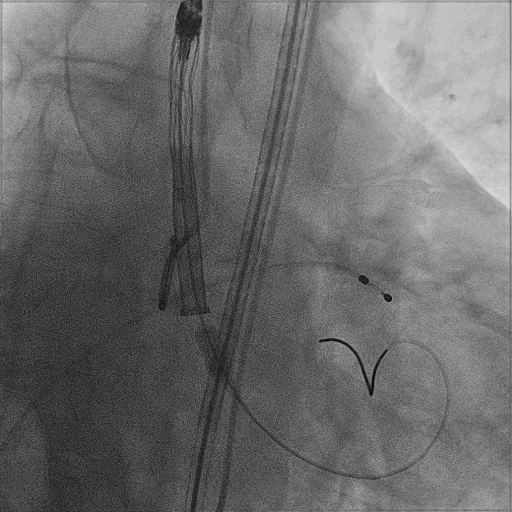

主动脉根部造影

22mm球囊预扩张

VitaFlow 27瓣膜精准定位

瓣膜形态良好,结果满意